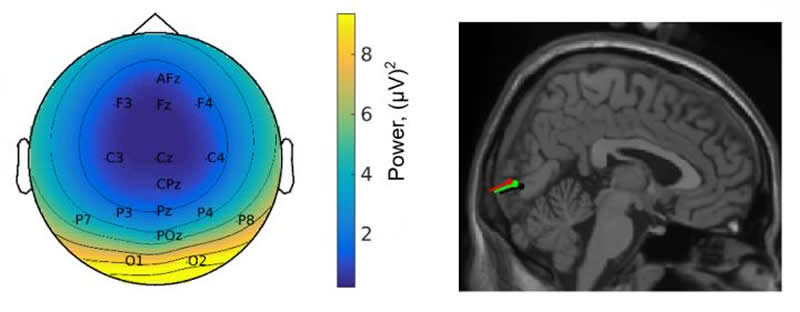

Mobile EEG, sensors and video glasses

It is precisely such gaps in knowledge that Barbara Händel wants to close with her work. In order to explore the link between movement and perception, sophisticated technical equipment is necessary. While the test subjects walk around, they wear electrode caps and a small amplifier that records their brain waves. The EEG data are sent wirelessly to a laptop, which the subjects carry in a backpack. Motion sensors, video glasses, and a mobile device for recording eye movements complete the setting.